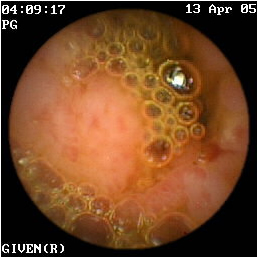

Η κάψουλα έχει επίσης ιδιαίτερη αξία στην ανεύρεση της εστίας της αιμορραγίας αγνώστου αιτιολογίας στη νόσο του Crohn (εικόνες 1,2). Οι Legnaniκαι συν του16 εκτίμησαν 11 ασθενείς με νόσο Crohnκαι αδιευκρίνιστη αιμορραγία και προσδιόρισαν την ακριβή αιτία της στους 9 από αυτούς.

1  2

Eικόνα 1. Βαριά φλεγμονή του βλεννογόνου             Εικόνα 2. Αυτόματη αιμορραγία ειλεού σε ασθενή

με σχηματισμό ψευδοπολύποδα.                             με γνωστή νόσο Crohn